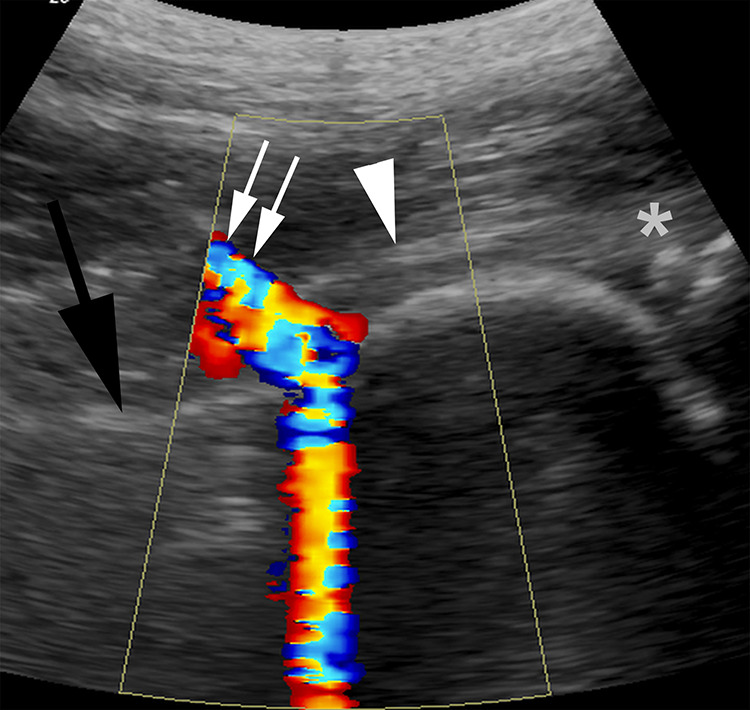

Background: Ultrasound guided hip injections have played a major role in the in-office diagnosis and treatment of a variety of traumatic and degenerative hip joint conditions. There is limited information as to the onset and duration of relief from these types of injections using a uniform medication combination.

Methods: We performed a retrospective study on 117 first time hip intraarticular injections performed by one operator using a single ultrasound machine and using the identical technique. In all cases, the hip joint was injected with 4 mL of 1% lidocaine and triamcinolone 40mg. The preinjection pain score was available in 98 hips with a mean of 6.4 ± 1.9 (mean ± S.D).